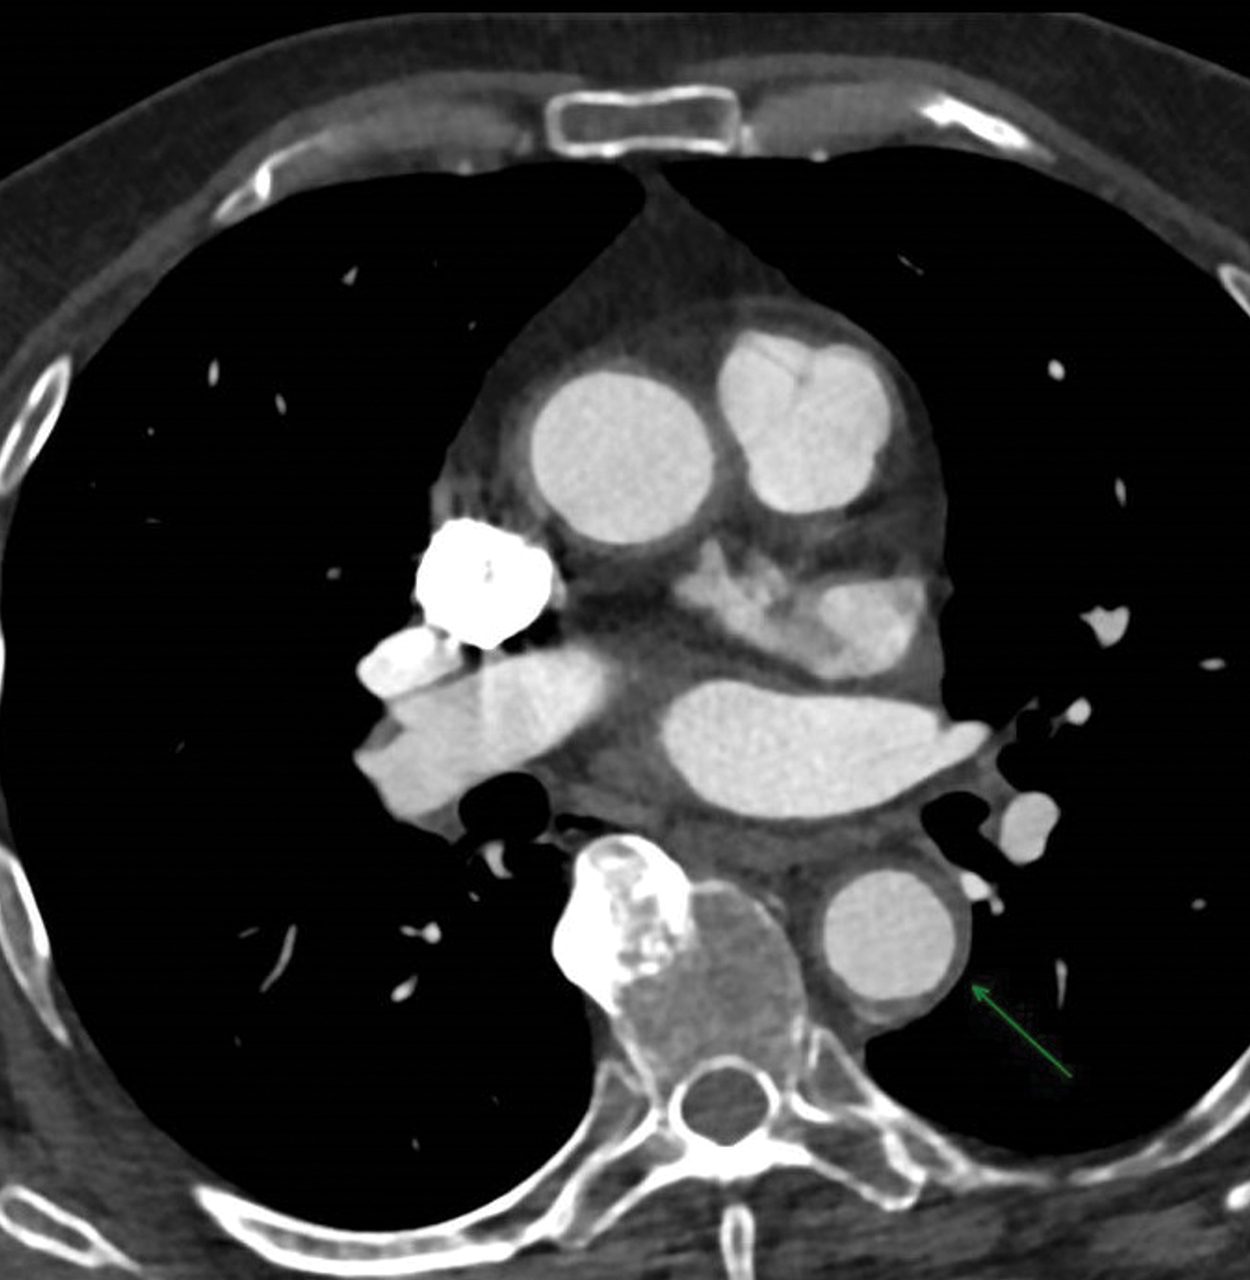

L’artérite à cellules géantes (maladie de Horton) est associée à la pseudopolyarthrite rhizomélique (PPR) dans 40 % des cas. Les douleurs des ceintures peuvent révéler la maladie. Les céphalées sont inconstantes dans les formes avec aortite. Le scanner permet d’objectiver l’aortite qui se traduit par un épaississement homogène de la paroi de l’aorte.